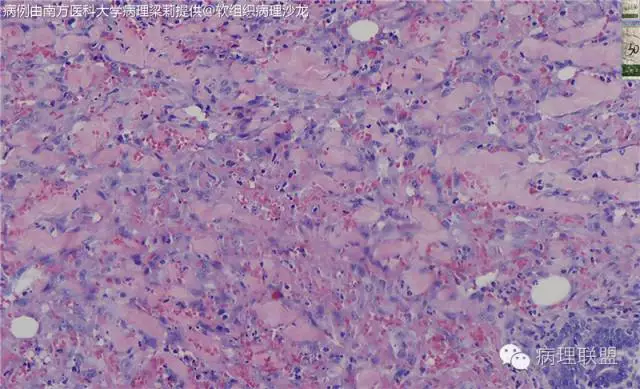

这例我们发的是卡波西样血管内皮细胞瘤,考虑如下:(1)新生儿,肢体肿物;(2)位置深,侵及皮下脂肪;(3)大多是裂隙状血管,也有少量吻合的血管网,细胞有异形,可见坏死

而复合性血管内皮瘤则是由良性、中间性和恶性的成份组成,也是浸润性生长,常常侵犯皮下脂肪组织,此例细胞形态由梭形细胞、卵圆形细胞及上皮样细胞组成,形态可见良性区域、中间性区域及高分化血管肉瘤或上皮样血管肉瘤区域,因此,似乎复合性血管内皮瘤更妥。此类肿瘤可以发生于婴幼儿。当然与Kaposi型血管内皮瘤一样,同属中间性血管瘤,只是后者,若肿瘤体积大,可出现Kasabach-Merritt综合征。

个人觉得应该是皮下纤维素渗出导致的内皮细胞旺炽性增生,局部呈内皮细胞乳头状增生,不认为是迷路样吻合;可能是婴幼儿血管瘤破裂诱发,也可能是血管畸形诱发。

注意活跃增生的内皮细胞总是与纤维素关系密切,并非穿插浸润的真皮胶原束。

混合型血管内皮瘤虽是混合各种形态,但是其主要成份一定是内皮瘤成份,上皮样血管内皮瘤或网状血管内皮瘤成份,其它血管肉瘤,血管瘤次要。@广医二院_病理科_梅开勇 仔细看了,好像是胶原。